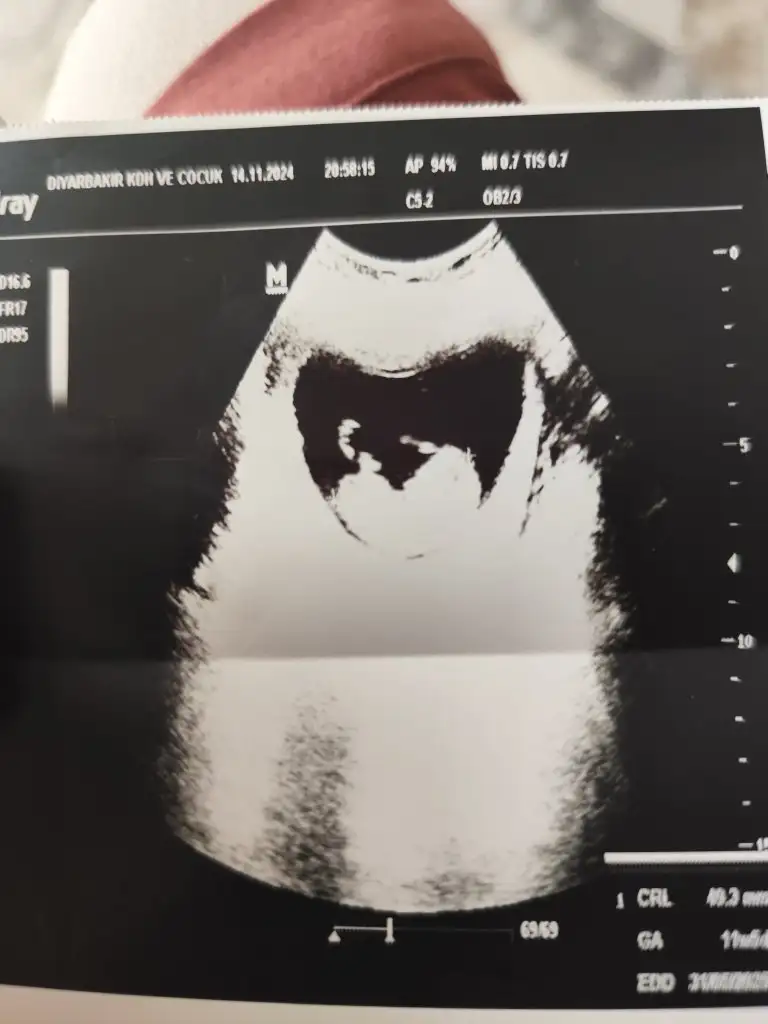

3. Erkek geliyorAmin insallah saglikli olsunlarda

Ayyyy saglikli olsunlarda .3. Erkek geliyorbugün baktırdım

İki kızım var hayırlısı olsunMerhaba bence kız

Rabbim gönlüne göre versin inşallah canım anlayamadığım için yorum yapamıyorum kaç haftalıksınİki kızım var hayırlısı olsun

Haftaya iyi bir doktora görünürsen belli olur canım sen ne hissediyorsunBana da